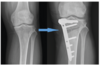

Patient had undergone right knee TKA 12 years ago, now complaining of sudden onset pain at the operated knee on ambulation. This is the plain radiograph of the symptomatic knee.

1. Describe the plain radiograph.

2. How will you investigate this patient to arrive to your clinical diagnosis?

3. What is the cause of this patient’s symptoms?

4. How will you manage this patient’s pain?

1. Plain radiograph

Right knee prosthesis is subluxed

Evidence of femoral and tibial osteolysis

• Tibia AP - > 2 mm radiolucent area beneath the tibial plate and cement interface.

• Femoral Lat - > 2 mm radiolucent area in the posterior condyles between femoral component and cement interface.

Change in position of implant - tibial component has flexed and varus subsidence.

** cement cracking/fragmentation and delamination

Re picture attached:

The classic loosening of the implant in worst instances begins with a delamination pull-away of the cement on the posterior keel, followed by failure of the proximal posterior tibial surfaces; Compare the positioning immediately post-op (a) verses that at 6 months, where the slope changes from 7o to 9o and the implant subsides (b)